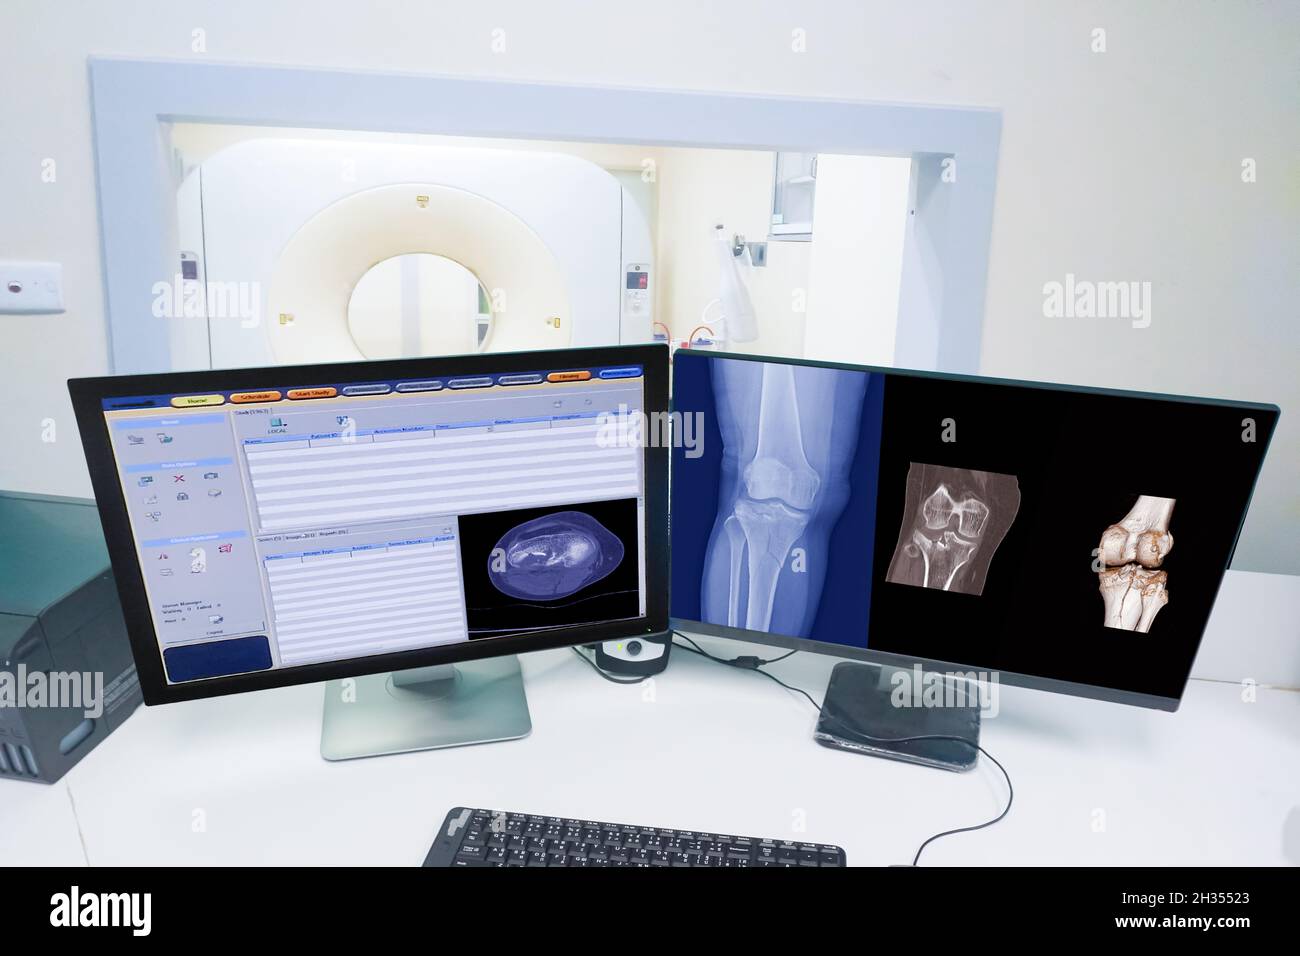

Close up Computer monitor Scan control room and computer showing knee scan fracture, Medical technology concept Stock Photohttps://www.alamy.com/image-license-details/?v=1https://www.alamy.com/close-up-computer-monitor-scan-control-room-and-computer-showing-knee-scan-fracture-medical-technology-concept-image449427275.html

Close up Computer monitor Scan control room and computer showing knee scan fracture, Medical technology concept Stock Photohttps://www.alamy.com/image-license-details/?v=1https://www.alamy.com/close-up-computer-monitor-scan-control-room-and-computer-showing-knee-scan-fracture-medical-technology-concept-image449427275.htmlRF2H35523–Close up Computer monitor Scan control room and computer showing knee scan fracture, Medical technology concept